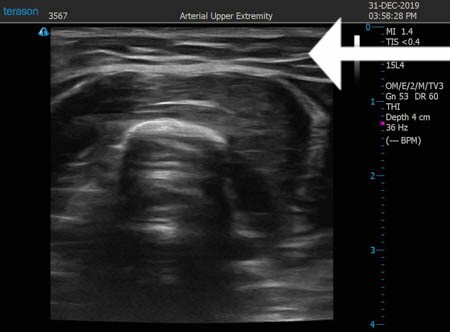

いつものように3Dタッチビュー(超音波)で

皮下脂肪層を評価してみましょう。

同様に左二の腕 ↓ ↓ ↓

↓ ↓ ↓